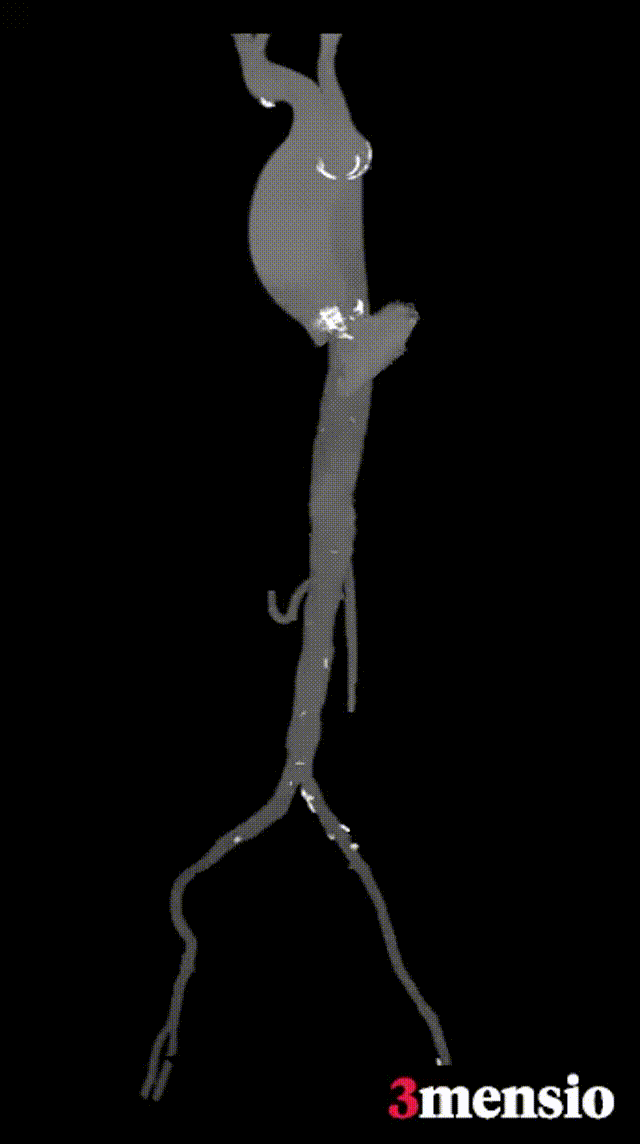

主动脉根部评估

根部概览

钙化概览

功能性二叶瓣,左无钙化融合,心室腔明显扩大。

多平面分析

敞口状流出道,瓣上限制较重,瓣膜释放后存在一定下滑风险。

冠脉分析

左冠开口较低,双侧瓣叶冗长,预估双侧冠脉均存在一定遮挡风险。

外周分析

外周概览(钙化)

外周概览

入路血管走形良好,无明显附壁钙化,弓部条件良好,预估过弓、跨瓣顺利。